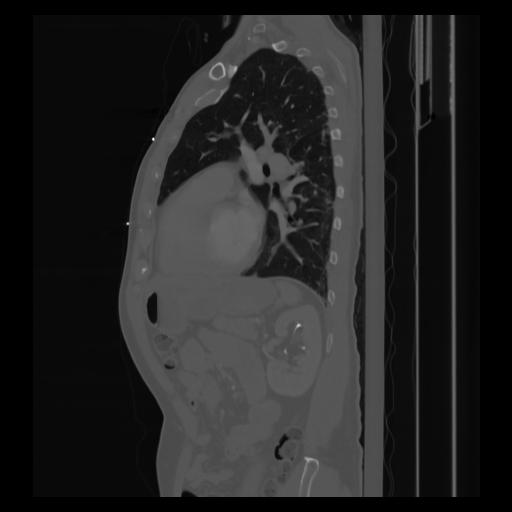

30 CUERPO,CE,Sagittal,3.000,CUERPO,Sagittal,